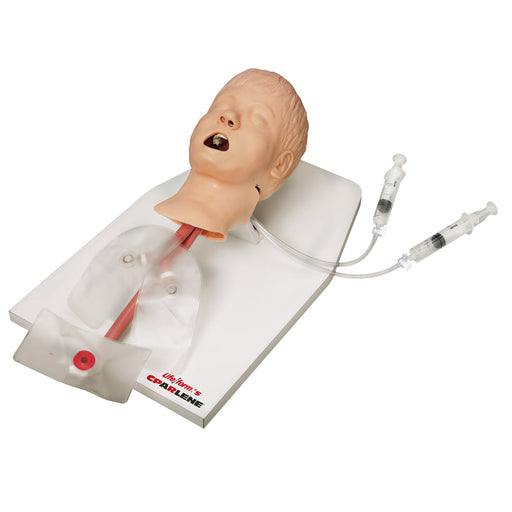

The VascularAccessChild Femoral Replacement Tissue is an ultrasoundable soft tissue that allows users to develop their skills in complete pediatric central venous catheterization of the femoral vein.

Use ultrasound to visualize cannulation, guidewire threading, and catheter placement. Practice palpating external landmarks to identify vessel location for blind/landmark insertion approaches.

- Anatomically correct, ultrasound compatible, femoral tissue with all relevant difficult palpating landmarks and vascular anatomy

- Red and blue simulated blood differentiate the arterial and venous vessels; provides immediate feedback on successful or unsuccessful cannulation

- Arterial pulse is present, and vein realistically compresses under palpation